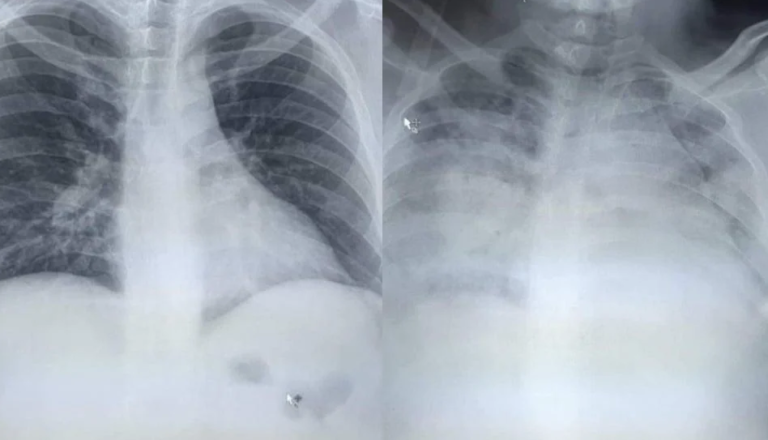

Hirurg iz Kragujevca dr. Vladimir Đorđević naTwitteru je objavio snimak pluća svog pacijenta koji je preminuo od posljedica teške upale pluća.

Pacijent je bio u tridesetim godinama i bio je srčani bolesnik, objasnio je dr. Đorđević, a vremenska razlika između dva snimka je samo 24 sata, piše Nova.rs.